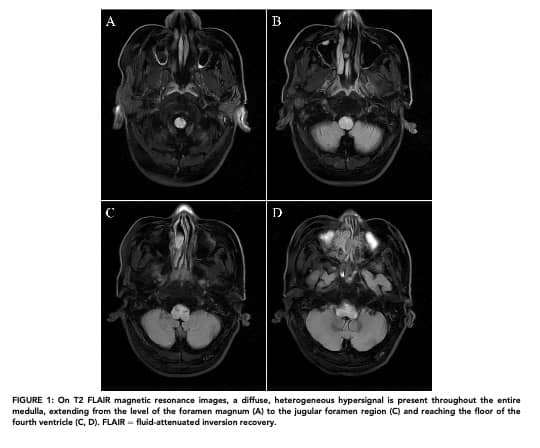

Cognard V 型 DAVF 是其中极为特殊且高危的 “少数派”:与常见的 I-IV 型颅内 DAVF 不同,它的 “异常短路” 连接在硬脑膜动脉与脊髓髓周静脉之间,相当于在脊髓关键血管网络里直接 “改道”。这种 “改道” 会直接导致静脉压力急剧升高(即静脉高压),若不及时治疗,静脉高压会引发一系列致命后果:进行性脊髓损伤、球麻痹(吞咽、发音等咽喉功能失灵)、呼吸障碍,甚至颅内出血——每一种都可能直接威胁生命。